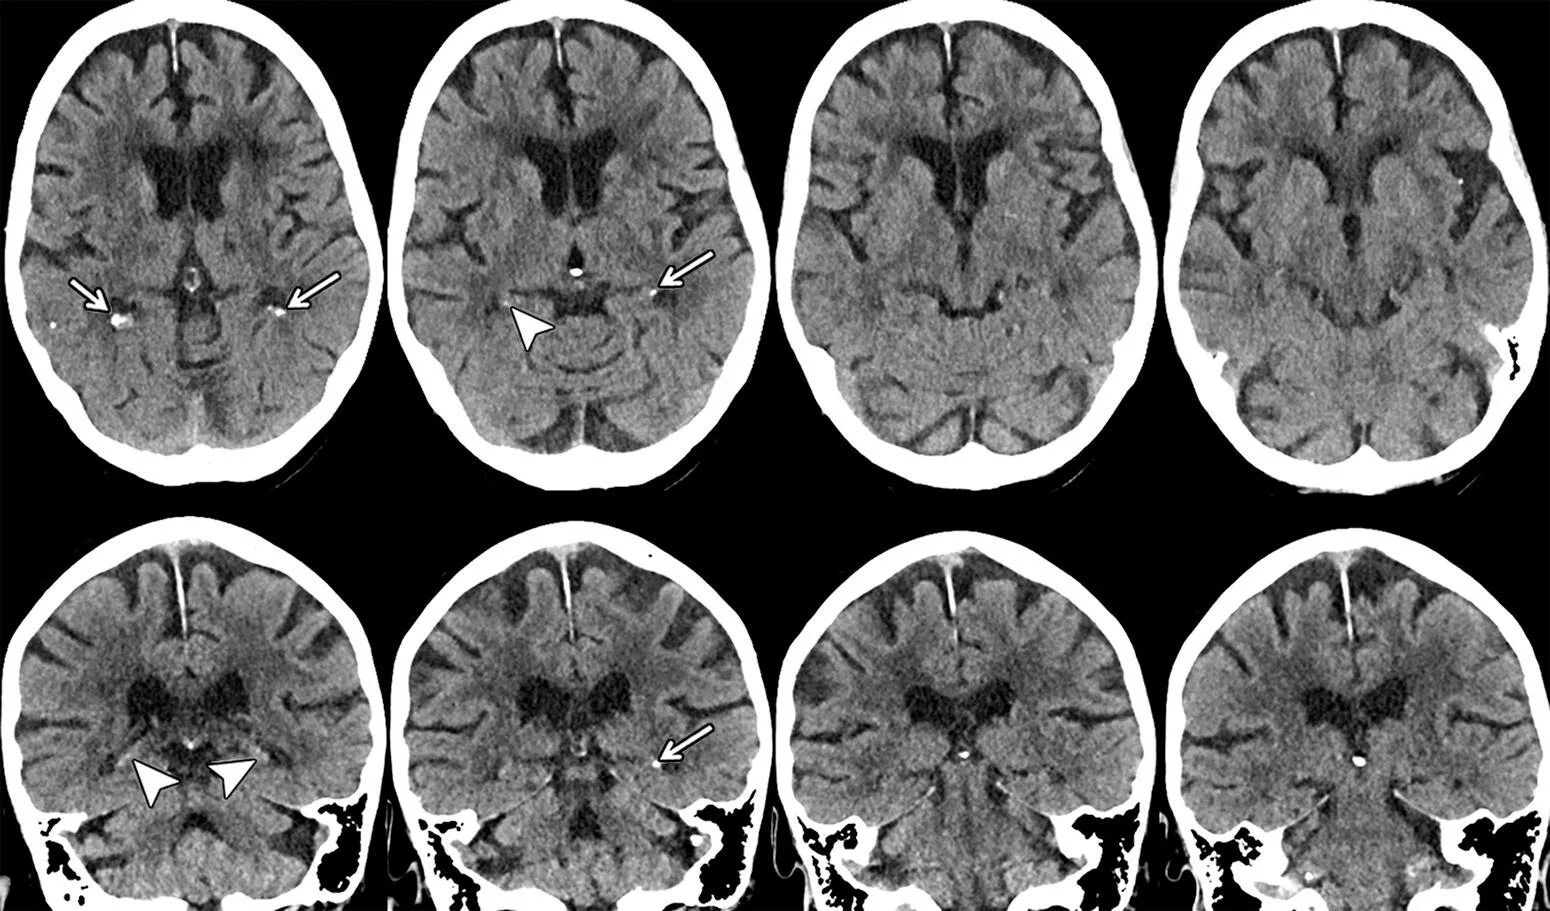

Микроангиопатия головного мозга симптомы